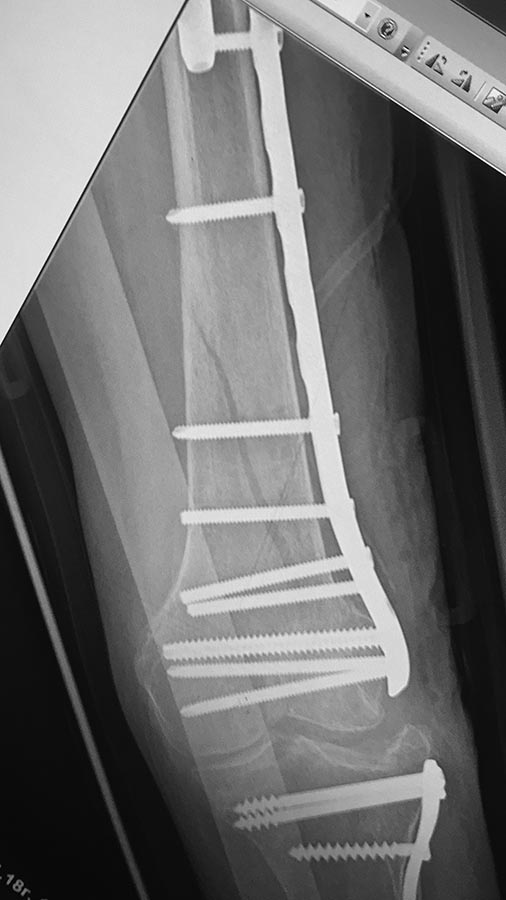

добрый день! вроде все получилось сделать,закрыто,чрезкожная остеотомия. дистальная пластина тоже малоинвазивно

бедро

Мыщелки2